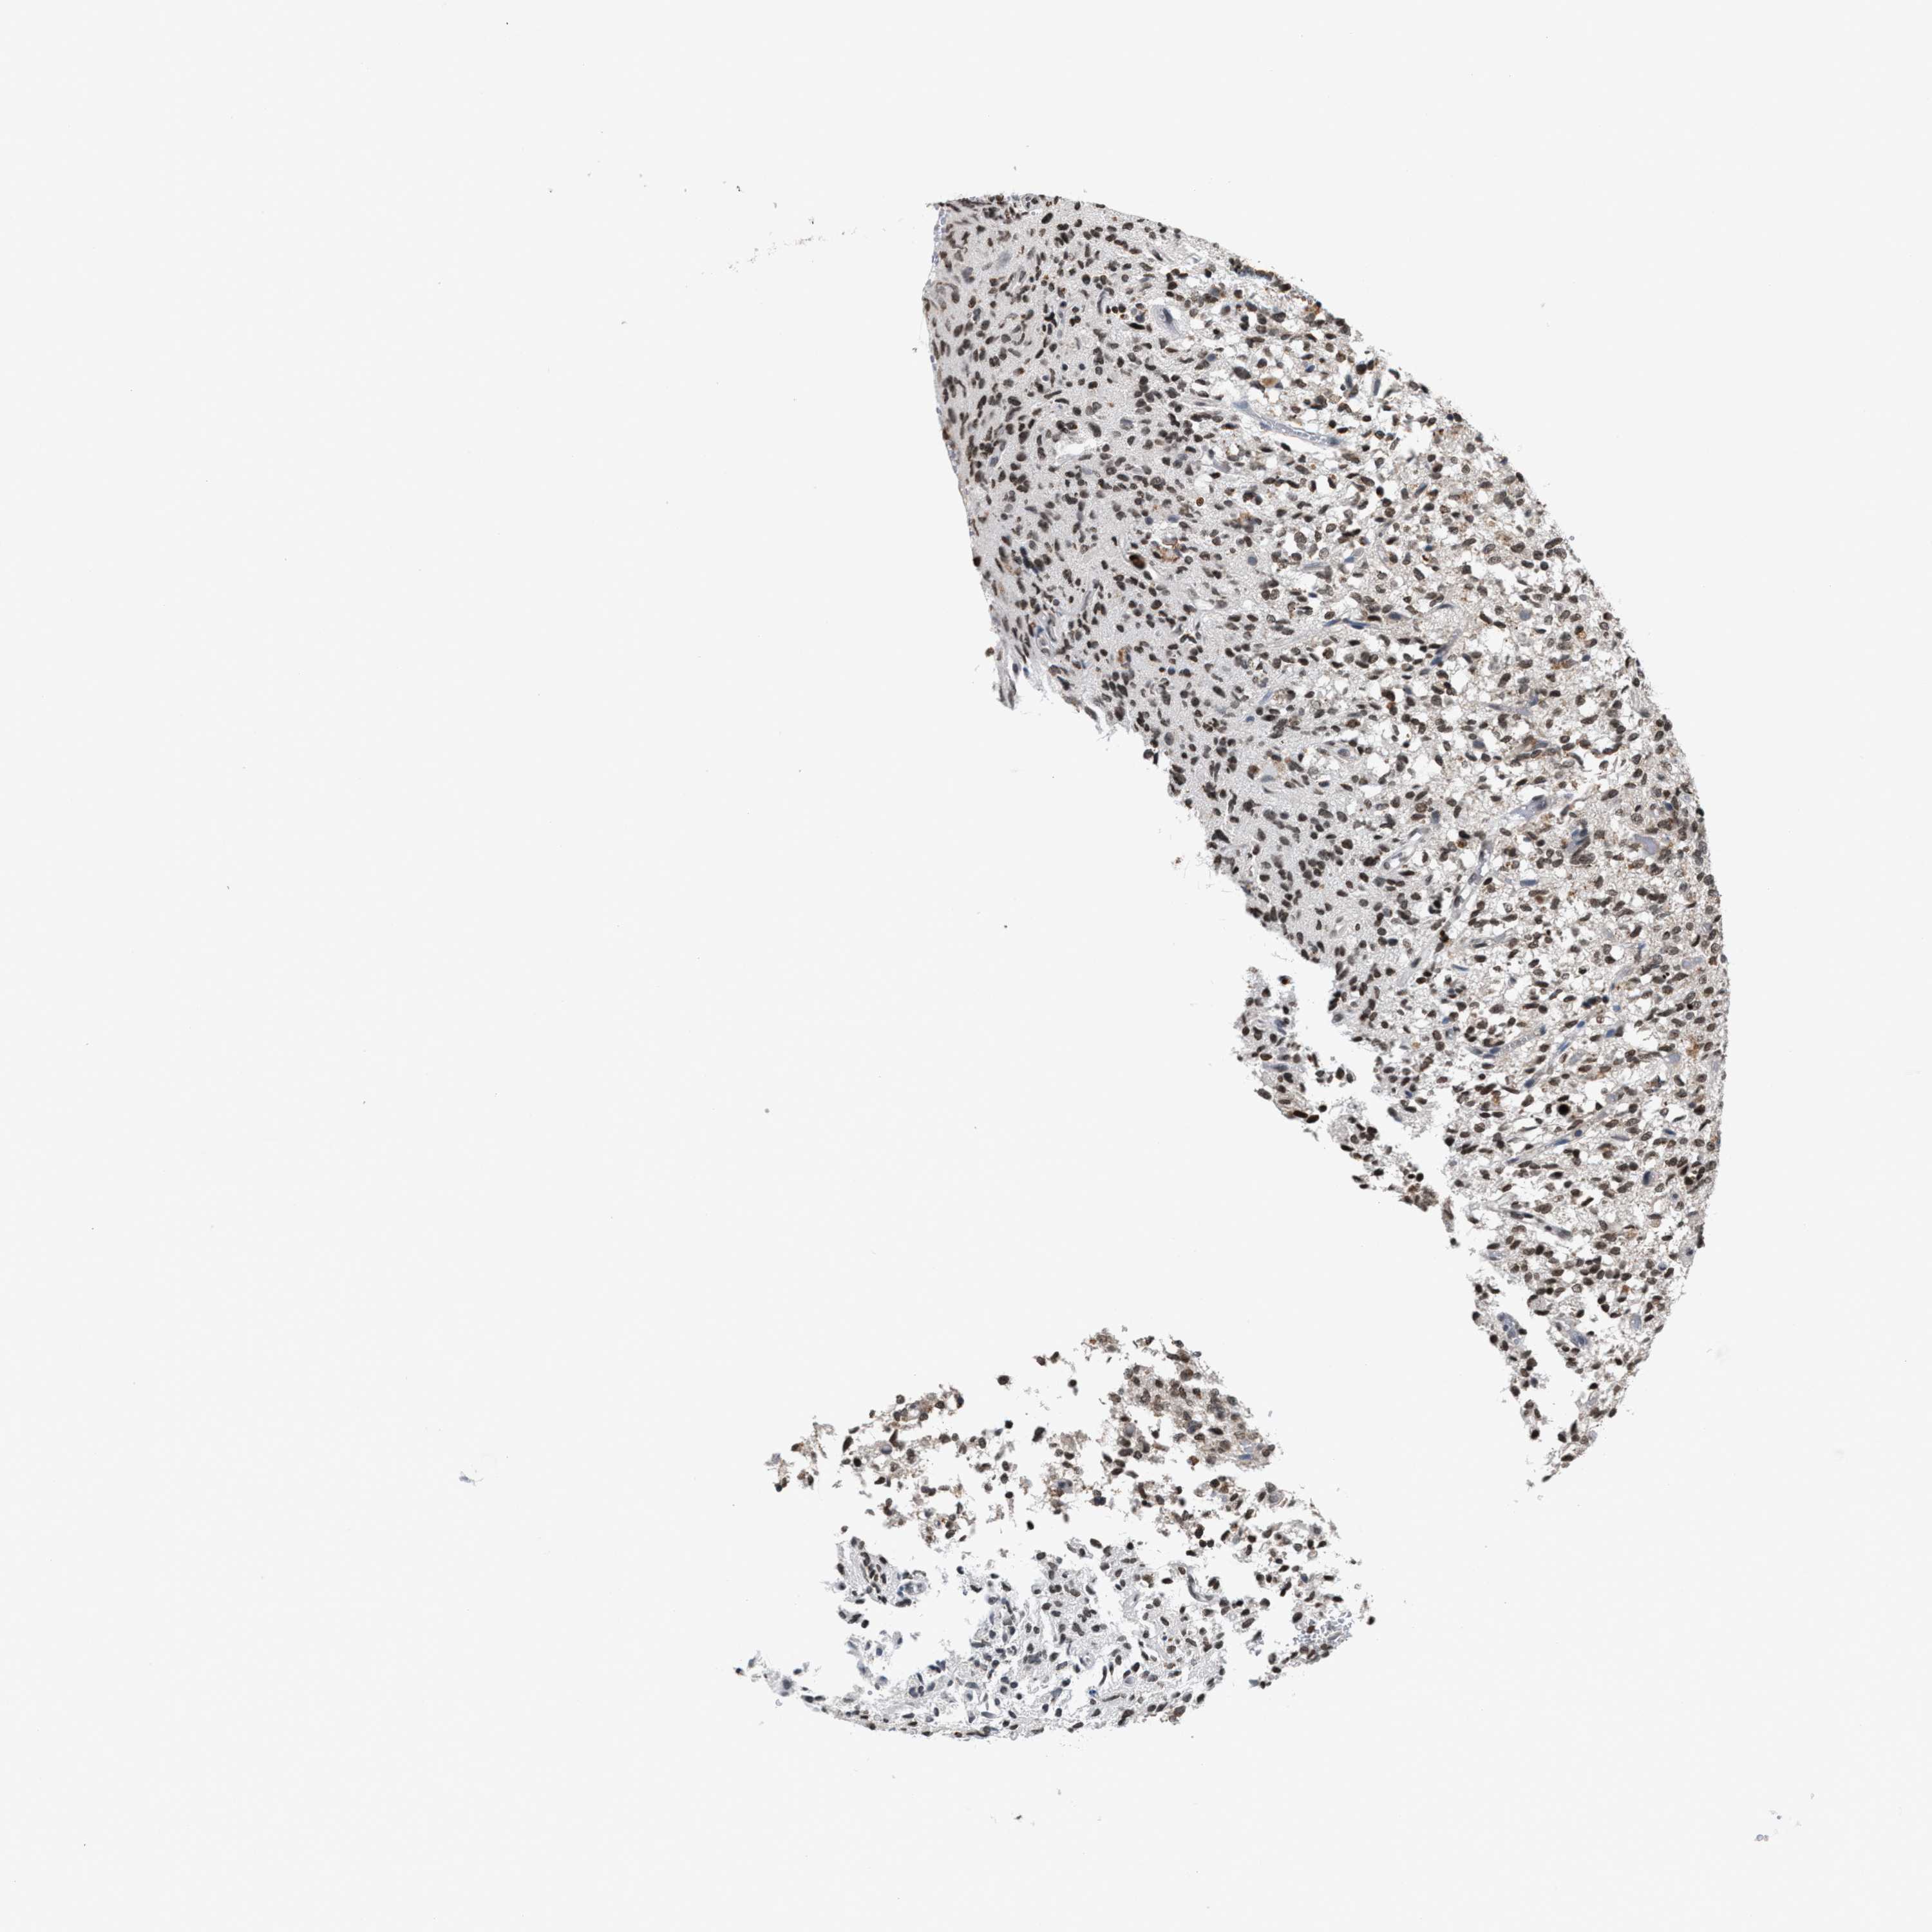

GLIOMA - Protein expressioni

A mouse-over function shows sample information and annotation data. Click on an image to view it in a full screen mode. Samples can be filtered based on level of antibody staining by selecting one or several of the following categories: high, medium, low and not detected. The assay and annotation is described here.

Note that samples used for immunohistochemistry by the Human Protein Atlas do not correspond to samples in the TCGA dataset.

Antibody stainingi

Antibody staining in the annotated cell types in the current human tissue is reported as not detected, low, medium, or high, based on conventional immunohistochemistry profiling in selected tissues. This score is based on the combination of the staining intensity and fraction of stained cells.

Each image is clickable and will lead to virtual microscopy that enables deeper exploration of all samples and also displays staining intensity scores, fraction scores and subcellular localization as well as patient and tissue information for each sample.

Antibody HPA022470

Antibody HPA031079

Staining

High

Medium

Low

Not detected

Intensity

Strong

Moderate

Weak

Negative

Quantity

>75%

75%-25%

<25%

None

Location

Nuclear

Cytoplasmic/membranous

Cytoplasmic/membranous,nuclear

Glioma, malignant, High grade

Glioma, malignant, Low grade

Glioblastoma, NOS